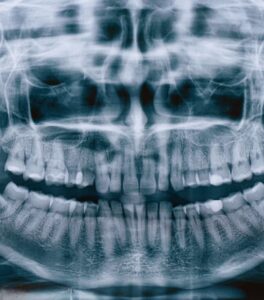

Панорамный снимок зубов – рентгеновское исследование, позволяющее получать двухмерное изображение нижней и верхней челюсти.

1. Панорамный снимок (ортопантомограмма, ОПТГ). Двухмерное изображение верхней и нижней челюсти. Развернутый снимок помогает оценить состояние ретинированного зуба, кисты, пломбы, нижнечелюстного состава, гайморовой пазухи. У врача появляется возможность составлять подробный план лечения, имплантации и протезирования. Разрешается проводить обследование в любом возрасте.